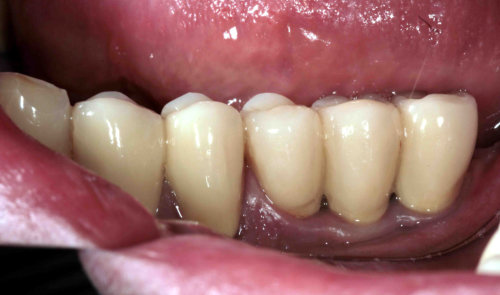

Implantate mit Aufbau für Kronen